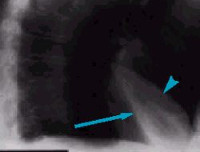

J98.1 Легочный коллапс